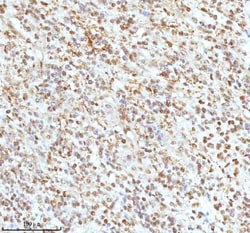

Reconstitute with 0.2 mL of distilled water to yield a concentration of 500 μg/mL. Positive Control - WB: human LNCAP whole cell, human Hela whole cell, human 293T whole cell, human HepG2 whole cell, human Jurkat whole cell, human K562 whole cell, human A549 whole cell, human A431 whole cell. IHC: human bladder cancer tissue, human bladder cancer tissue, human colon adenocarcinoma tissue, human colon adenocarcinoma tissue, human glioblastoma tissue, human glioblastoma tissue, human liver cancer tissue, human liver cancer tissue, human lung adenocarcinoma tissue, human lung adenocarcinoma tissue, human pancreas ductal adenocarcinoma tissue, human pancreas ductal adenocarcinoma tissue, human testicular seminoma tissue, human testicular seminoma tissue. ICC/IF: U2OS cell. Flow: A431 cell. Store at -20°C for one year from date of receipt. After reconstitution, at 4°C for one month. It can also be aliquotted and stored frozen at -20°C for six months. Avoid repeated freeze-thaw cycles.